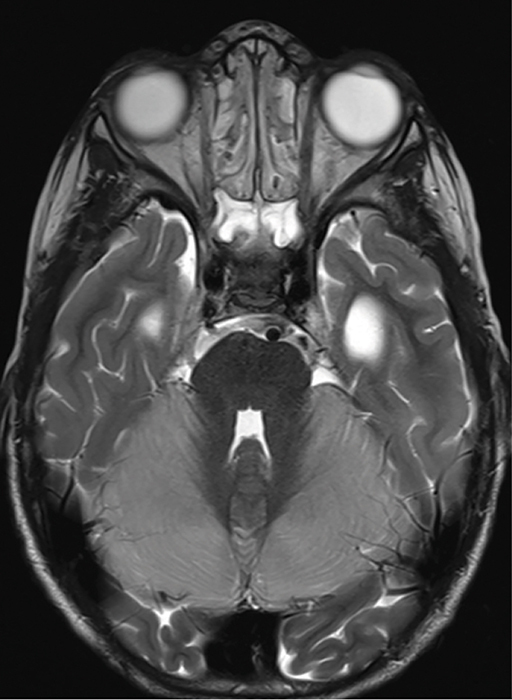

We report the case of a 4‑year‑old child who experienced rapid neurological decline following opioid administration during anesthesia for an interventional procedure to treat a vein of Galen aneurysm. Cerebral magnetic resonance imaging (MRI) revealed marked cytotoxic edema in both cerebellar hemispheres and the brainstem, indicative of opioid‑induced neurotoxicity. A follow‑up MRI, performed 2 weeks later, showed profound cerebellar and brainstem atrophy and showed reduction in mass effect due to cytotoxic edema. Teaching point: Pediatric opioid‑use‑associated neurotoxicity with cerebellar edema (POUNCE) syndrome is a rare condition, characterized by cerebellar edema as a hallmark feature, which can be identified on MRI in pediatric patients following opioid use.

Abstract Image